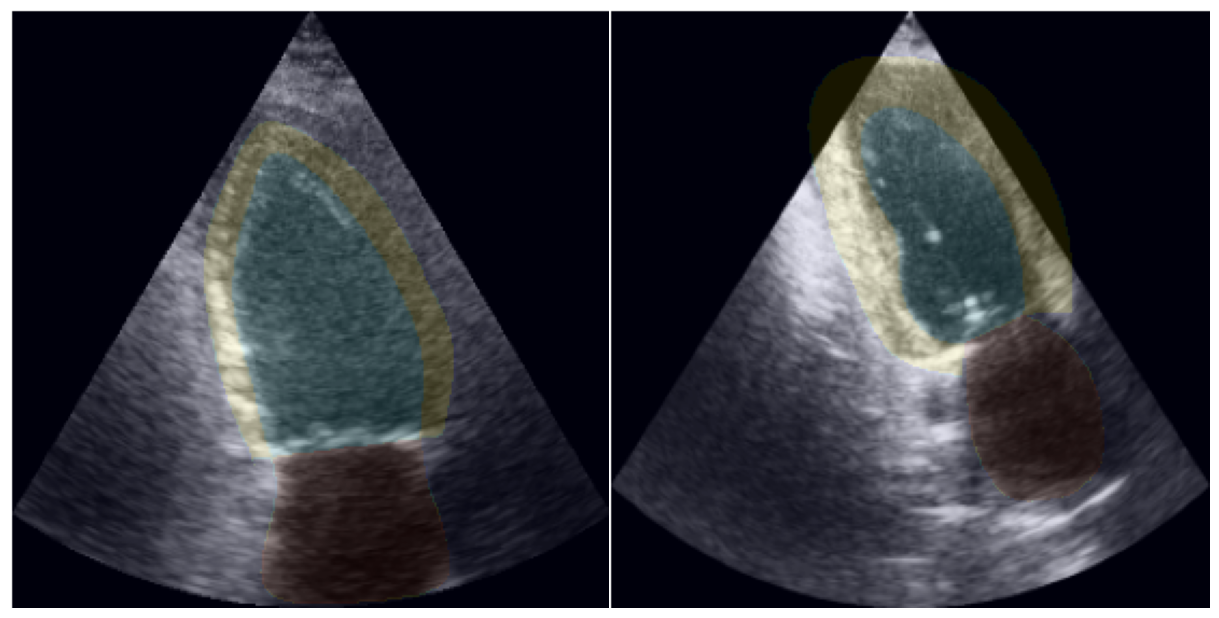

Although both HUNT4 and CAMUS present the same clinical views, the two datasets cannot be directly combined and jointly trained on due to differences in annotation conventions and imaging techniques. In CAMUS, the myocardium is annotated significantly thicker than in HUNT4, as illustrated in Figure 1. Additionally, HUNT4 images have less variance in terms of positioning and are regarded as more standardized [5].

Figure 1: Ground truth segmentations from HUNT4 (left) and CAMUS (right). Images from HUNT4 are consistently LV-focused, while those from CAMUS are not.